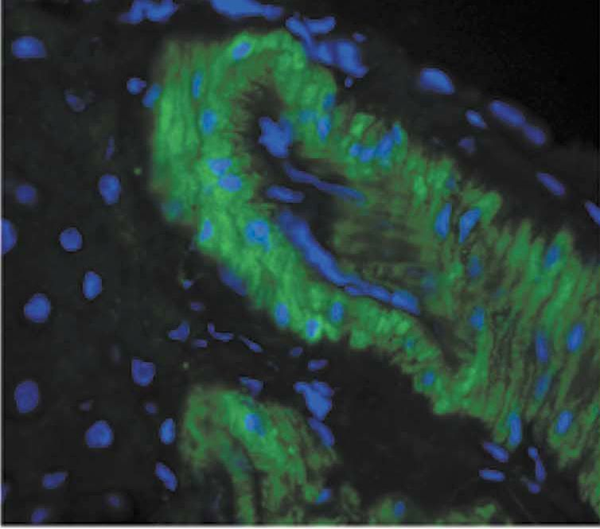

IHC (Immunohistochemisry)

(Immunohistochemistry analysis using Mouse Anti-Nitrotyrosine Monoclonal Antibody, Clone 39B6. Tissue: liver tissue . Species: Rat. Primary Antibody: Mouse Anti-Nitrotyrosine Monoclonal Antibody at 1:1000. Secondary Antibody: FITC Goat Anti-Mouse (green).)